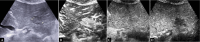

Intrahepatic cholangiocarcinoma (ICC) is a rare, heterogeneous, highly lethal tumor of the biliary tract. Due to the lack of effective treatments, an early identification of ICC is essential to achieve the best outcome in terms of therapy and prognosis aiming for a curative intent. ICC may arise on a normal liver or with an underlying liver disease, making the diagnosis more difficult and complex. Contrast-enhancement ultrasound (CEUS) is an accurate procedure able to detect ICC-specific contrast vascular pattern, and thus facilitating the correlation between radiological and histopathological findings with high specificity and sensitivity. CEUS has been shown to have a high diagnostic potential in the diagnosis of ICC thanks to the possibility of studying in real time the intralesional microcirculation and evaluating the precocity of the enhancement of the lesion during the arterial phase. All these features allow to differentiate the ICC from hepatocarcinoma (HCC) with high sensitivity and specificity. Furthermore, CEUS is a rapid, non-invasive, non-nephrotoxic or non-allergenic tool. The only limitations CEUS may have are related to the disease site and patient characteristics (obesity) and compliance, including the operator's experience. A clinical evaluation of the patient, together with tumor markers and biochemical tests assessment, to differentiate ICC from HCC are highly suggested.